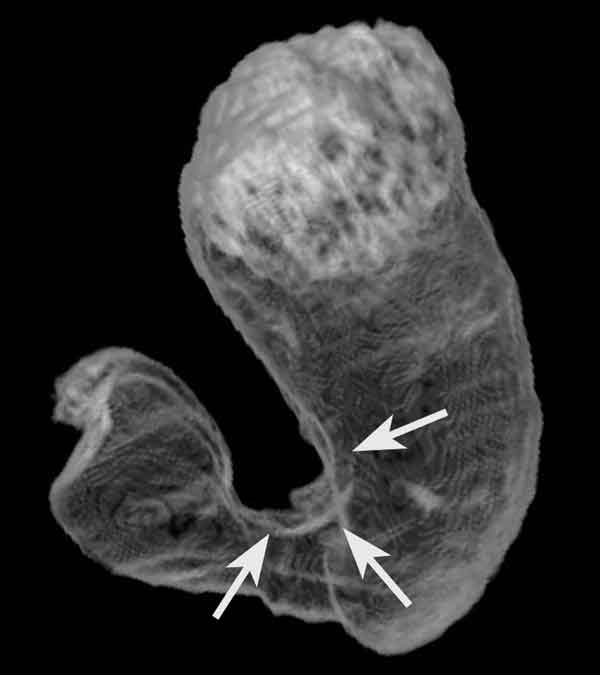

l sapore, forse, non sarà dei più gradevoli. Tuttavia, gli effetti sulle ulcere allo stomaco, a quanto pare, sono davvero antincendio. La sperimentazione sull’estratto liquido del tubero avviata dall’Università di Manchester un po’ per caso e grazie alla saggezza di una nonna sta dando i suoi frutti e si candida a diventare un integratore naturale nella battaglia contro le ulcere gastriche.

L’intuizione è partita da un microbiologo del dipartimento durante il pranzo della Domenica. “La nonna di uno dei nostri ricercatori – ricorda Ian Roberts – durante il pranzo in famiglia gli ha confessato di usare le patate per curare le sue ulcere”. Il giovane scienziato è corso a comprare un sacco di patate nel negozio più vicino, portandolo poi in laboratorio, “nell’incredulità di tutti”, spiega Roberts al Daily Mail. Da lì è cominciata la caccia vera e propria del team alla molecola “antincendio” della nonna che è scaturita nella selezione delle varietà migliori.

Alla fine la scelta è caduta su due tuberi, Maris Piper e Kind Edward, che sembrano avere le proprietà antibatteriche più efficaci. L’obiettivo dello staff inglese è sviluppare un succo gradevole da bere, simile ad uno yogurt probiotico. “Pensiamo che il succo di patata potrebbe funzionare come misura preventiva per fermare le ulcere gastriche – aggiunge Roberts –, una sostanza che la gente potrebbe assumere come parte di uno stile di vita sano”. Le ulcere gastriche, infatti, in circa la metà dei pazienti sono causate Helicobacter pylori, un batterio che si localizza al di sotto della mucosa, ma anche alcol, caffè e grassi, oltre allo stress, possono predisporre alla patologia.